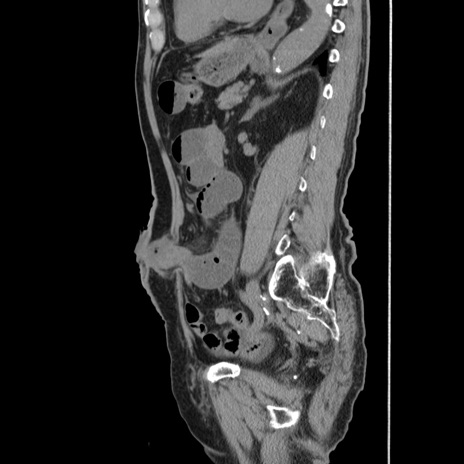

症例24(矢状断像)

【症例】80歳代男性

【主訴】左側腹部痛、嘔吐

【現病歴】本日早朝より左腹部に痛みあり。昼頃嘔吐認めたため、救急要請。

【既往歴】直腸癌(Mile手術)、胆摘

【身体所見】意識清明、BT 35.9℃、BP 221/93mmHg、SpO2 97%(RA) 、腹部:左ストーマ周囲に限局性の腹部膨隆あり。 膨隆部自発痛・圧痛あり・軟。

【データ】WBC 7700、CRP 0.09